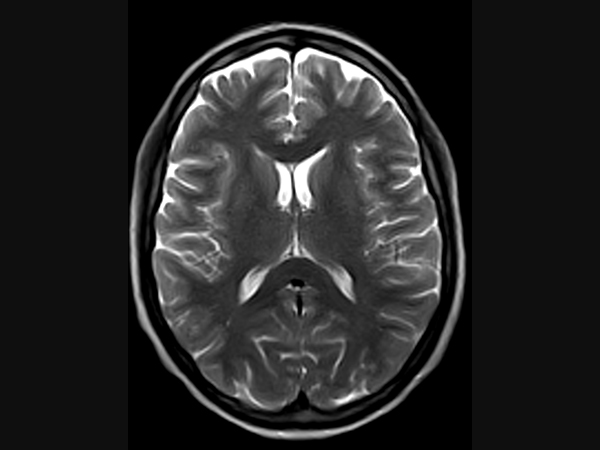

Klinické snímky

Technologie, příslušenství a snímky

G-scan Brio je speciálně navržen pro všechny aplikace pohybového aparátu. Otevřený a naklápěcí design je nový a inovativní způsob provádění MRI, při kterém se poloha pacienta stává nedílnou součástí výsledku vyšetření. G-scan Brio poskytuje pacientovi vysoký komfort s funkcí nejnovějšího zobrazovacího výkonu a sekvencí společnosti Esaote.